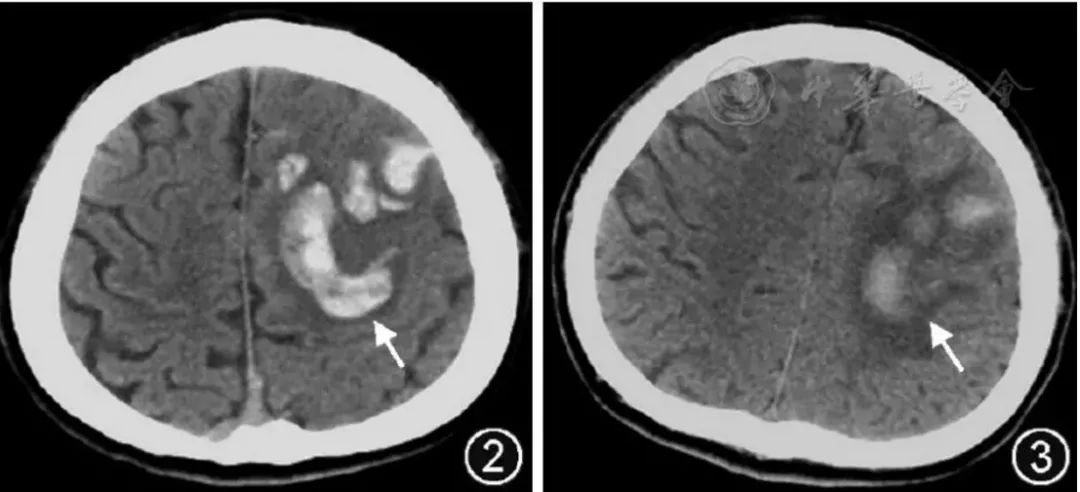

33岁男性,携带艾滋病毒,进行性加重的嗜睡、腹泻、腹痛和失明。

轴向DWI 显示侧脑室室管膜表面弥散受限(A)。相应的T1WI有轻微增强(B)。FLAIR (C)及T1WI 增强扫描(D)显示两侧葡萄膜增厚,右侧视网膜脱离。

成人机会性巨细胞病毒脑室脑炎的影像学表现是非特异性的。巨细胞病毒性视网膜炎和胃肠道受累是巨细胞病毒性感染的常见形式,但在所有巨细胞病毒性感染患者中,神经系统表现仅占不到1%。临床表现为:定向障碍、淡漠、退缩、颅神经病和眼球震颤。脑室脑炎是CMV感染中最常见的中枢神经系统受累形式,其特征是脑室内表面的室管膜炎。CMV引起的视网膜炎发生在大约三分之一没有接受HAART治疗的艾滋病患者中,并占与艾滋病毒感染相关的失明病例的90%以上。主要诊断特征:沿室管膜表面弥散受限伴/不伴造影增强。脉络膜视网膜炎表现为葡萄膜增强、视网膜脱离和视网膜钙化。巨细胞病毒引起的视网膜炎最常见于单眼,并进展到累及对侧眼。要与淋巴瘤和化脓性脑室炎相互鉴别。